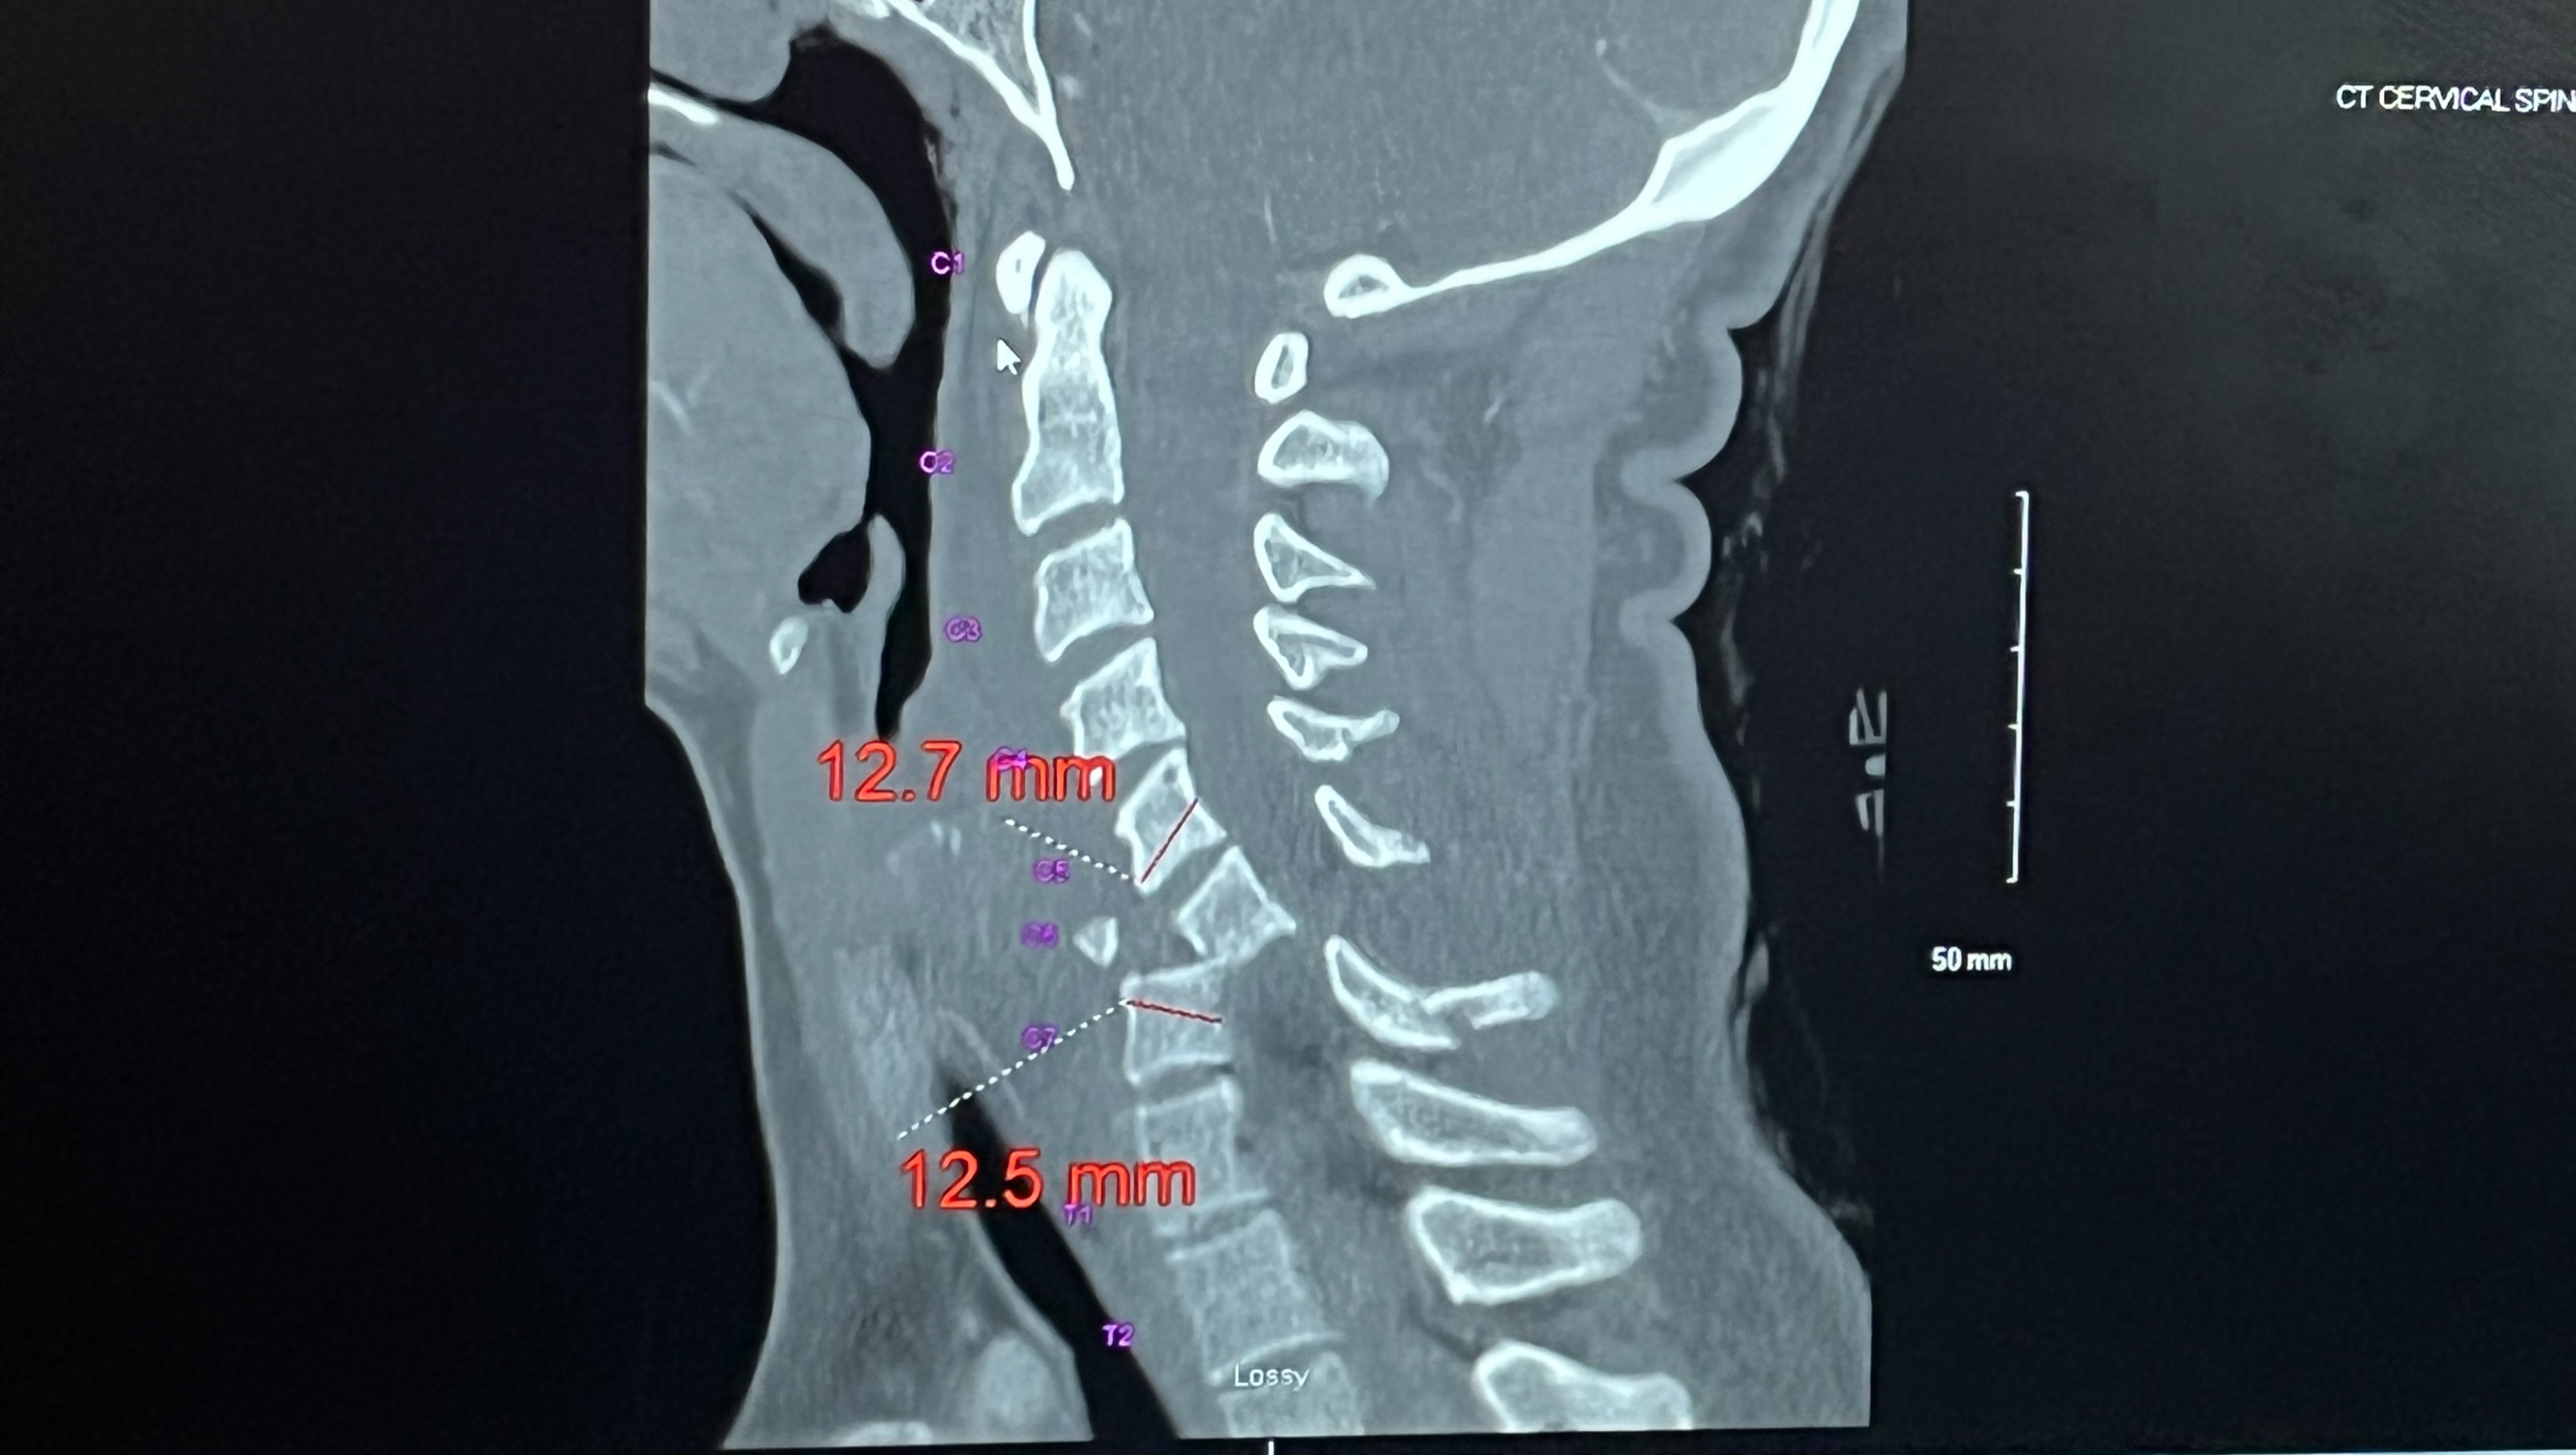

For those that are familiar with spinal cord injuries will likely know the degree of impact that severing your spinal cord at your c6 vertebrae will have on your everyday life. For those that don't, it means I no longer have any mobility in my legs, feeling in my lower abdomen, or full use of my hands.